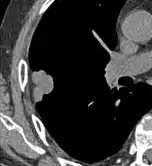

Lobulated nodule.[9]

Spiculated lung nodule.[9]